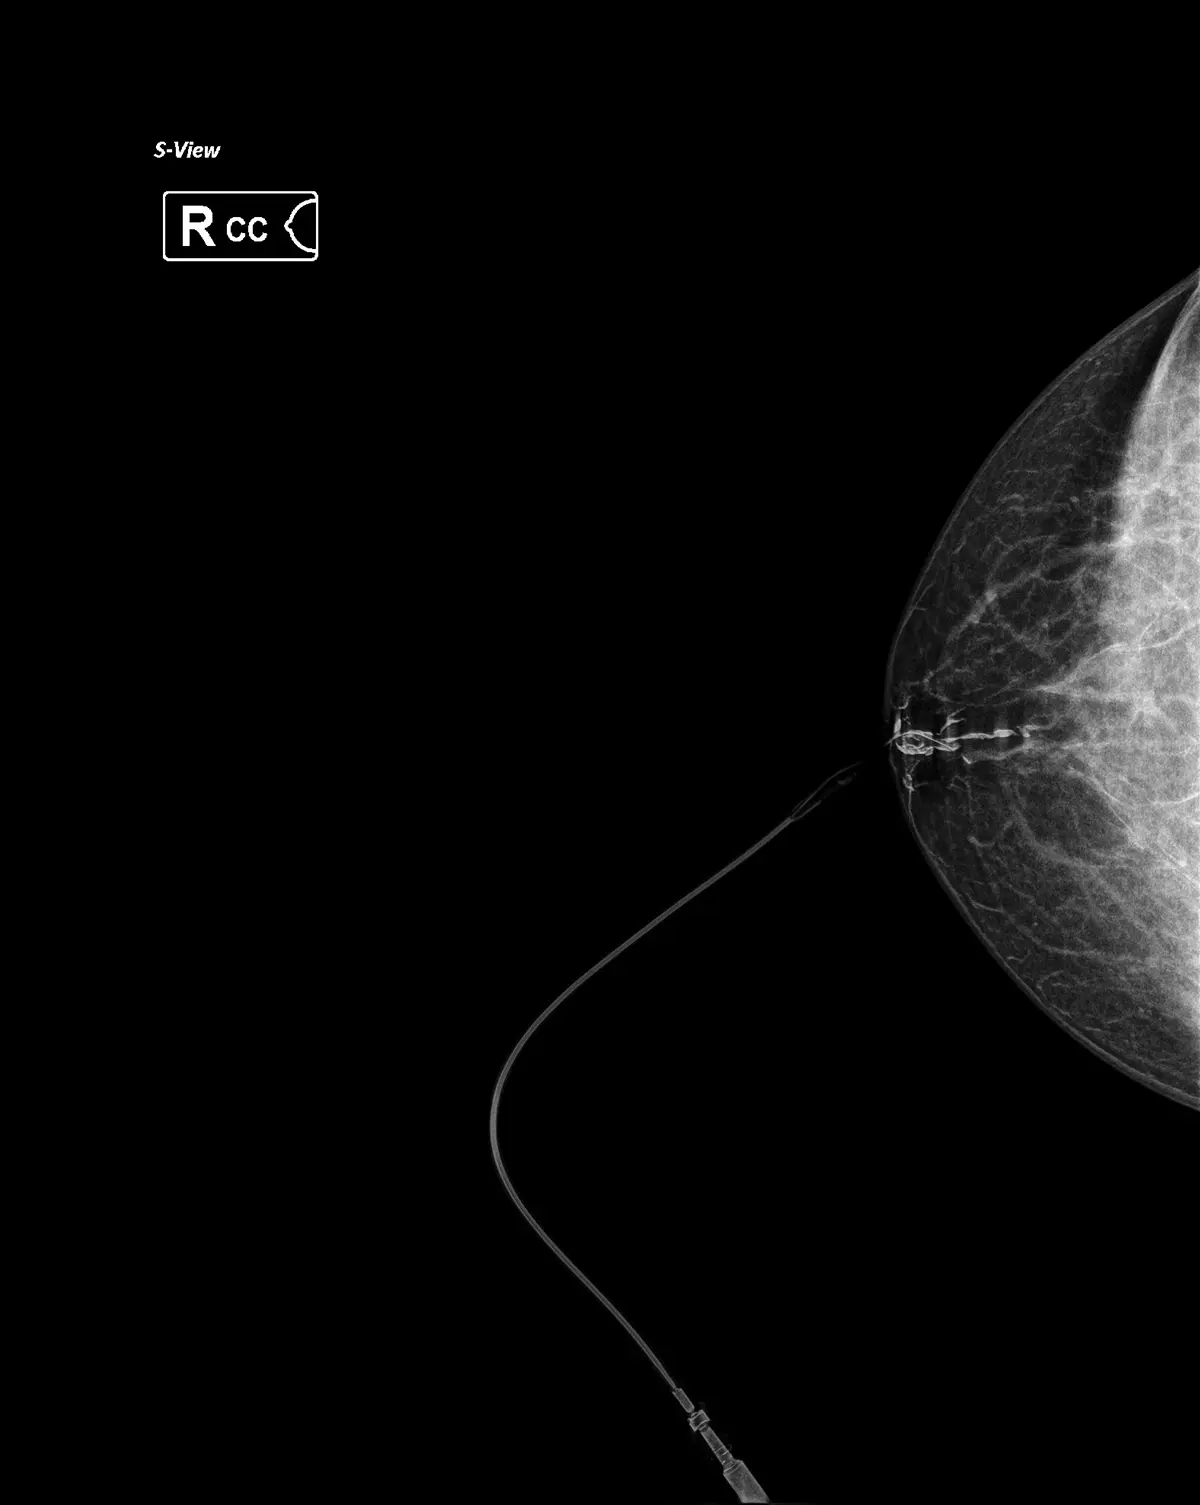

Galactography is an X-ray examination in which a small amount of contrast medium is applied directly into the milk duct from which the discharge is coming, after which a targeted mammography is performed.

1. A contrast medium is applied using a thin catheter

2. A targeted mammographic image is taken

3. The examination takes a short time and is performed on an outpatient basis

The examination is minimally uncomfortable, without the need for general anesthesia.